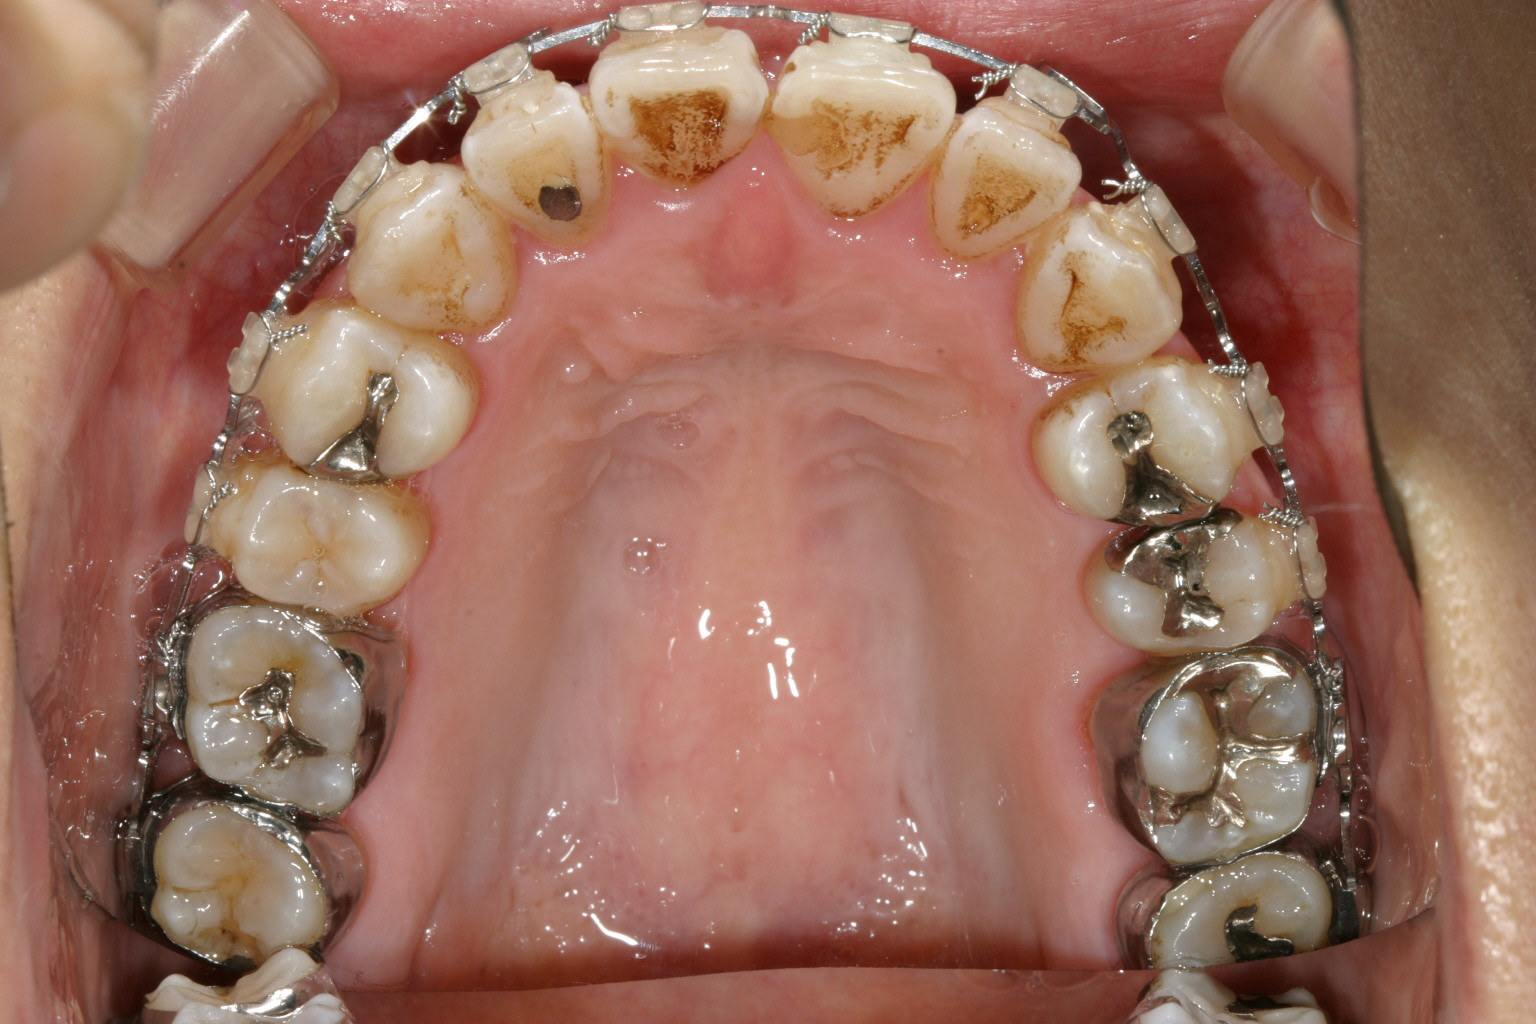

1年2か月後です。 マルチループが入っています。アーチの形状は殆ど改善致しました。

下顎もマルチループの外側に太いマリガンワイヤーが入っています、この太いワイヤーのお陰で内方に倒れていた臼歯が立ってきました。